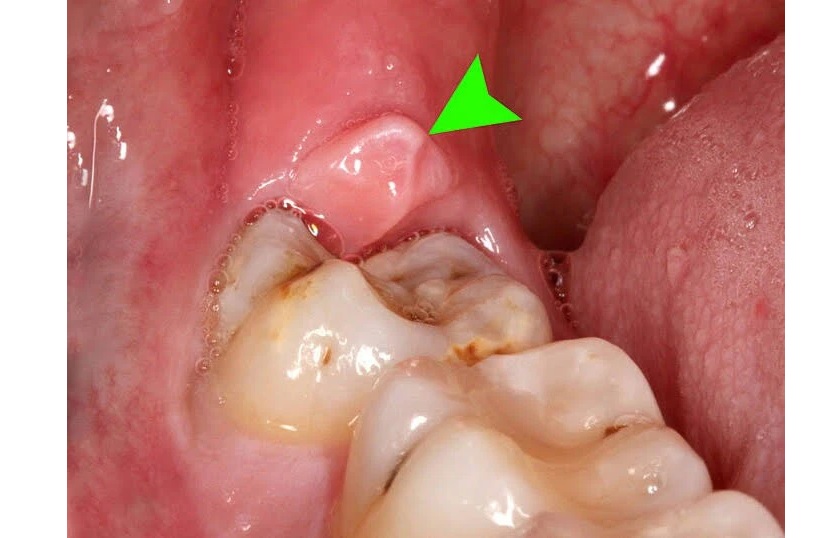

Khi chiếc răng khôn nhú lên, phần nướu phía dưới có thể sưng lên và gây đau, có thể nhận thấy ở các răng kế bên. Cơn đau này có thể diễn ra trong vài ngày và sau đó biến mất trong vài tuần hoặc vài tháng trước khi quay trở lại. Thông thường, mức độ đau sẽ tăng dần nếu bạn không tiến hành điều trị từ sớm.

Khi răng khôn mọc lên một phần có thể tích tụ thức ăn, mảng bám và các mảnh vụn khác, dẫn đến sưng nướu, sâu răng và nhiễm trùng quanh răng.

Viêm nướu răng là một trong những bệnh nhiễm trùng, trong đó vi khuẩn từ thức ăn, mảng bám và các mảnh vụn khác bị giắt giữa khoảng trống của răng bị va đập và nướu. Nếu không được điều trị sớm, tình trạng nhiễm trùng này có thể lây lan về phía cổ họng hoặc vào cổ.

Viêm nướu răng do mọc răng khôn gây ra